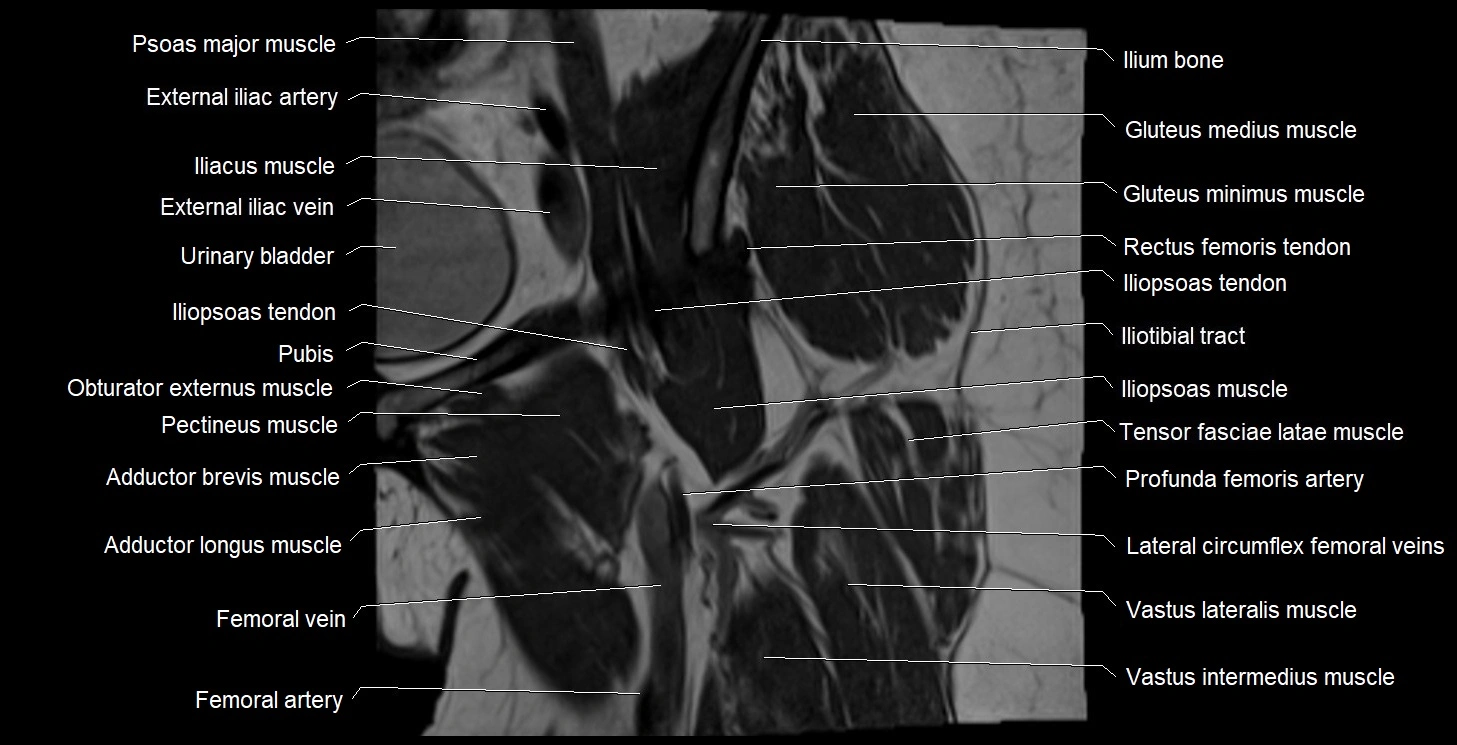

- External iliac artery

- External iliac vein

- Femoral artery

- Femoral vein

- Iliopsoas muscle

- Iliopsoas tendon

- Iliotibial tract

- Ilium bone

- Lateral circumflex femoral veins

- Pectineus muscle

- Psoas major muscle

- Tensor fasciae latae muscle

- Vastus intermedius muscle

- Vastus lateralis muscle